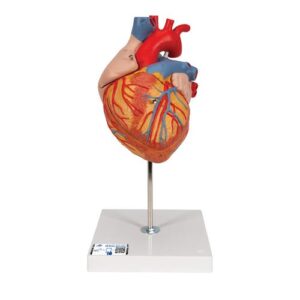

This realistic model shows the anatomy of the liver and gall bladder. The Liver with gall bladder shows:

4 lobes with gall bladder

Extrahepatic ducts

Hilus vessels

This high quality liver with gallbladder replica is delivered on removable stand.

- Shows: 4 lobes with gall bladder, Extrahepatic ducts, Hilus vessels

- Size: 18x18x12cm

Liver and Gall bladder properties featured:

- Liver

- Right lobe of liver

- Left lobe of liver

- Quadrate lobe

- Caudate lobe

- Proper hepatic artery

- Hepatic portal vein

- Common hepatic duct

- Neck of gallbladder

- Gallbladder